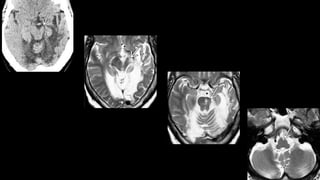

Degeneração olivar hipertrófica

Núcleo denteado

Triangulo de Guillain-Mollaret

Pós-cirúrgico de meduloblastoma no

núcleo denteado do lado direito

Infarto mesencéfalo

Núcleo denteado Núcleo denteado Núcleodenteado Triangulo de Guillain-Mollaret

Pós-cirúrgico de meduloblastomano núcleo denteado do lado direito